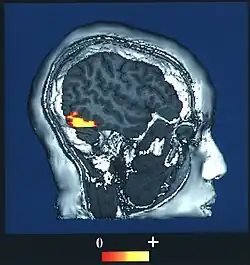

A side-on image of an fMRI scan of a human brain.

A computer-enhanced fMRI scan of a person who has been asked to look at faces

Facial perception has neuroanatomical correlates in the brain.

The fusiform face area (BA37— Brodmann area 37) is located in the lateral fusiform gyrus. It is thought that this area is involved in holistic processing of faces and it is sensitive to the presence of facial parts as well as the configuration of these parts. The fusiform face area is also necessary for successful face detection and identification. This is supported by fMRI activation and studies on prosopagnosia, which involves lesions in the fusiform face area.[34][35][36][37][38]